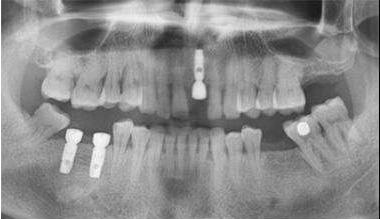

"种植牙"

传统种植牙通常需要4-6个月的愈合期,这对我们日常生活中正常的牙齿使用会带来很大的影响,所以现在大部分有种植牙需要的患者都会选择——即刻负重种植牙。

即刻负重种植牙就是指种植体在植入的同时,马上就以以安装临时义齿的行为;

虽然根据义齿制作的复杂程度会有最长72小时的延时,但是即刻负重种植牙是目前最好的可以最大限度满足患者对牙齿美观程度和功能方面要求的治疗方案。

即刻负重种植牙有很多优点,但不是所有人都可以做的,需要经过专业的检测达标后才可以进行种植:

1.患者骨密度质量达到I、II、III号骨质。 2.患者种植体植入的部位有达标厚度的皮质骨,且有足够的健康附着牙龈; 3.患者的种植区域有可以满足种植体植入后不会产生缺损的骨量; 4.患者的种植体的长度在10毫米以上,直径在3.5毫米以上。且可以采用表面经过处理粗糙的阶梯状或者是螺旋状的种植体。